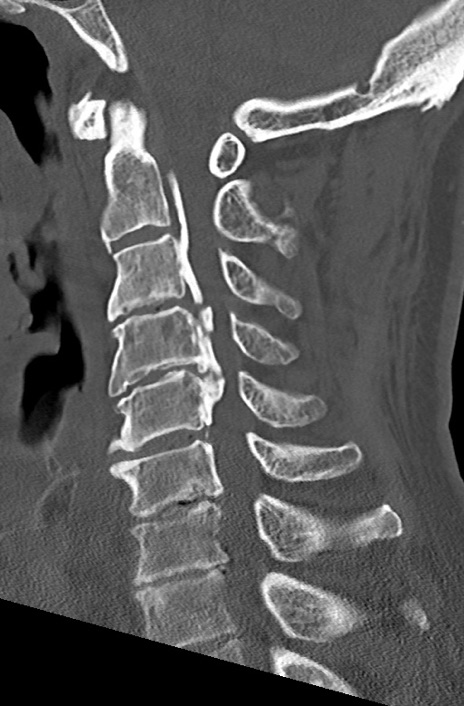

頚椎CT

矢状断像と横断像